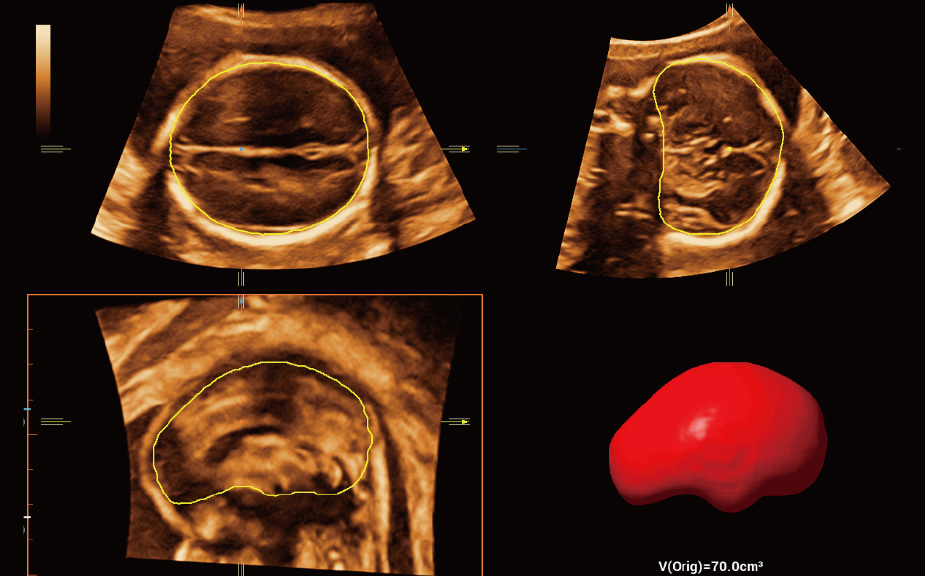

Intelligenza completa orientata allo scenario clinico

L'innovativa soluzione Smart Scene 3D consente l'identificazione automatica delle caratteristiche dei tessuti e fornisce una diagnosi specifica per i diversi distretti di esame durante l'intera procedura. Questa innovazione aumenta lŌĆÖaccuratezza e la sicurezza diagnostica, migliorando lŌĆÖefficienza.